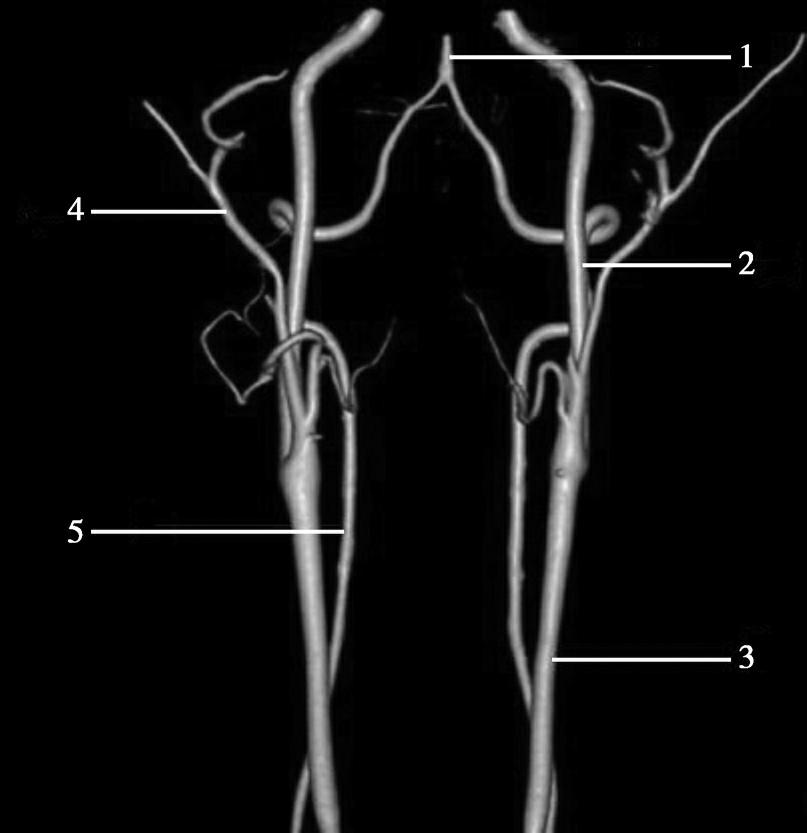

CT血管成像(CT angiography,CTA及CT venography,CTV)通过三维重建技术可显示颅内动静脉的走行、血管壁及血管周围等情况(图1-2-73~图1-2-75)。

图1-2-73 正常颅脑CTA

1.大脑前动脉;2.大脑中动脉;3.颈内动脉;4.大脑后动脉;5.基底动脉;6.椎动脉

图1-2-74 正常椎基底动脉CTA

1.基底动脉;2.颈内动脉;3.颈总动脉;4.颈外动脉;5.椎动脉